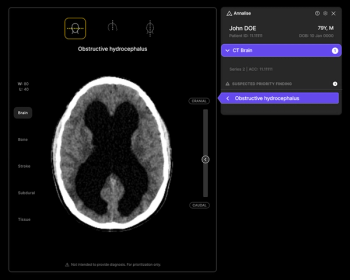

Featuring 12 prior FDA clearances for chest X-ray and non-contrast head CT, the Annalise Triage platform may help streamline radiology workflows and prioritize timely diagnosis of urgent conditions.